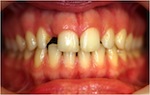

vorher

nachher

Patientin – 29 Jahre, Angle Kl. I, Invisalign für 9,5 Monate

Persistierender 52

(hier bereits entfernt)

12 war distal von 52 durchgebrochen